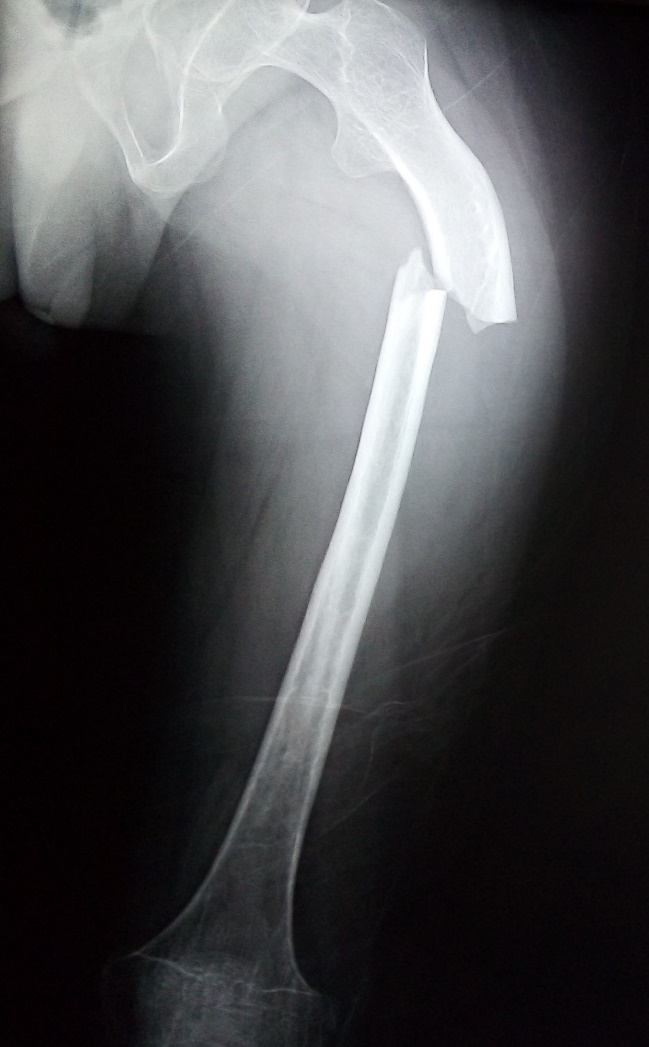

Figura 1. Radiografía AP de miembro pélvico izquierdo, se muestra fractura y alteración en la densidad del hueso.

Examen físico: signos vitales dentro de parámetros normales. Cara en forma triangular, escleras blancas, limitación a la flexo extensión de cuello, escoliosis dorso lumbar, tórax en tonel, amplexión y amplexación disminuidas, ruidos cardiacos rítmicos, de buena intensidad y frecuencia, abdomen blando, depresible, no doloroso, curvatura anormal en extremidades superiores, cicatrices y deformación en ambas extremidades inferiores, Daniels 1/5 en miembros pélvico izquierdo, Daniels 3/5 en miembro pélvico derecho, llenado capilar menor a dos segundos, sin edema.

Figura 2. Radiografía AP de miembro pélvico, se muestra fractura y alteraciones en la densidad del hueso.